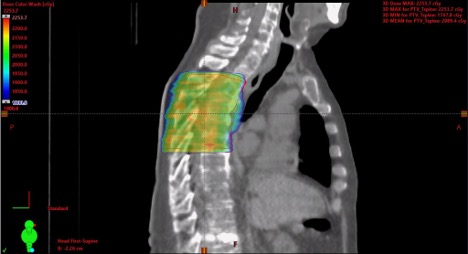

13/20 #TumorBoardTuesday 📋Back to our case 65M with de novo low-volume mCSPC Prostate RT 5500 cGy ⚡ in 20 fractions SBRT 2000 cGy ⚡X5 fractions to T7 and L3 mets SBRT 4000 cGy ⚡ X5 fractions to L iliac met

13/20 #TumorBoardTuesday

đź“‹Back to our case

65M with de novo low-volume mCSPC

Prostate RT 5500 cGy ⚡ in 20 fractions

SBRT 2000 cGy ⚡X5 fractions to T7 and L3 mets

SBRT 4000 cGy ⚡ X5 fractions to L iliac met